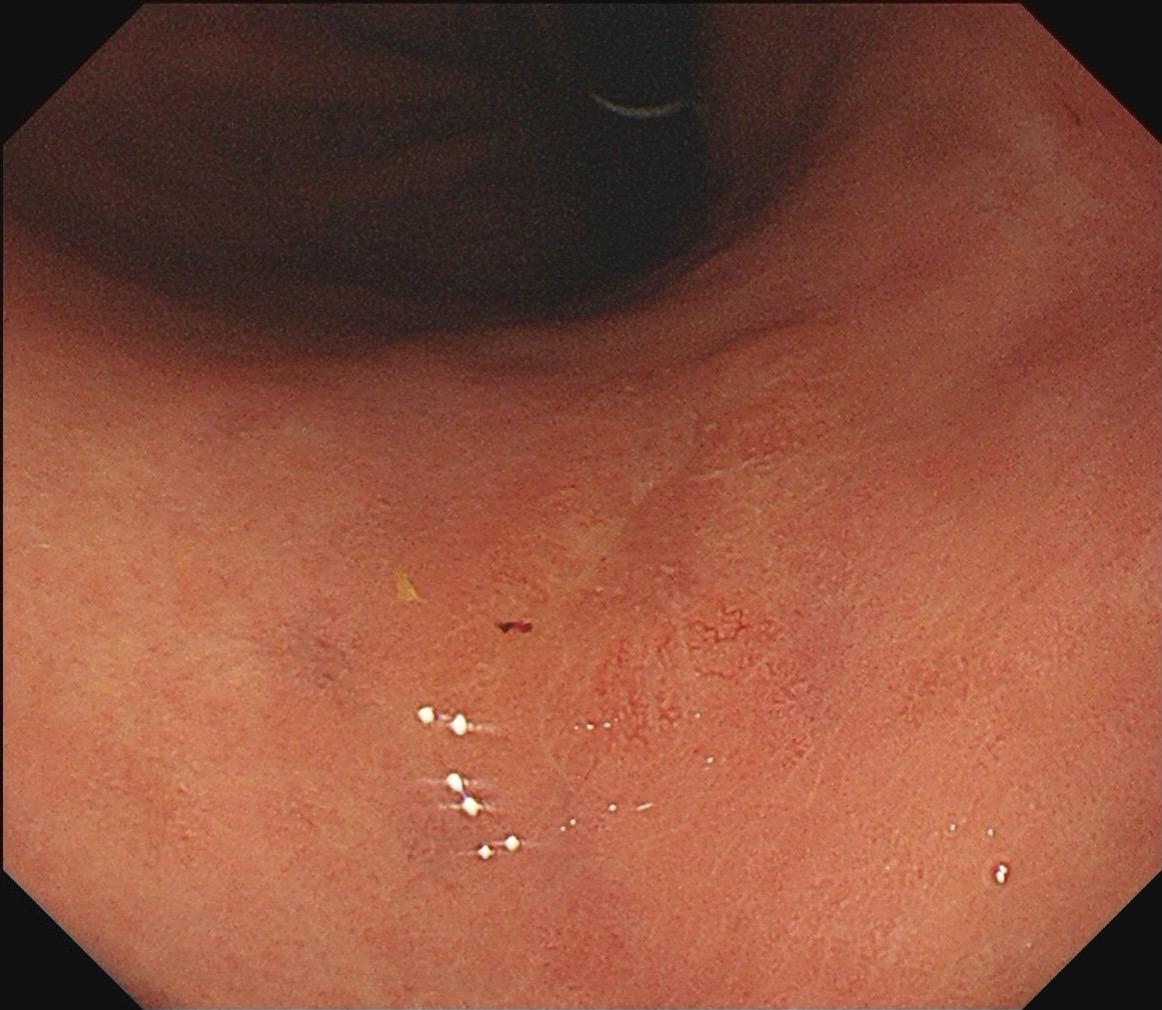

萎缩背景中的褪色调。泾清渭浊,匪恃目明,静验其枢。

2025-09-29 13:05